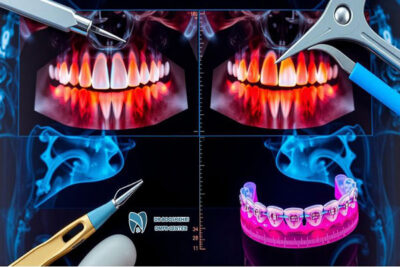

Several types of radiography are utilized in dental orthodontics, each serving a specific role and application. The most important types of radiography used in orthodontics include:

- Panoramic Radiography: Provides an overview of the entire mouth and jaws.

- Cephalometric Radiography: Used to assess the relationship between teeth and jaws and the overall structure of the face.

- Periapical Radiography: Used for detailed views of teeth from crown to root.

- Bitewing Radiography: Employed to examine cavities and spacing between teeth.

Each of these radiographies has a unique role in identifying various issues and optimizing treatment plans.